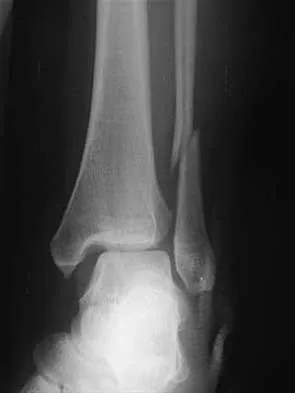

Figures 4a through 4c show the radiographs of a 43-year-old woman who sustained a twisting injury to her right ankle. She has ankle pain and tenderness medially and laterally. To help determine the optimal treatment, an external rotation stress radiograph of the ankle is obtained. This test is designed to evaluate the integrity of what structure?

In the presence of a supination external rotation-type fracture of the distal fibula (Weber type B), stability of the ankle is best assessed by performing an external rotation stress AP view of the ankle. This test is used to assess the integrity of the deltoid ligament. The presence of a deltoid ligament rupture results in instability and generally is best managed surgically. The gravity stress test can also be used. Egol KA, Amirtharajah M, Tejwani NC, et al: Ankle stress test for predicting the need for surgical fixation of isolated fibular fractures. J Bone Joint Surg Am 2004;86:2393-2398. McConnell T, Creevy W, Tornetta P III: Stress examination of supination external rotation-type fibular fractures. J Bone Joint Surg Am 2004;86:2171-2178.